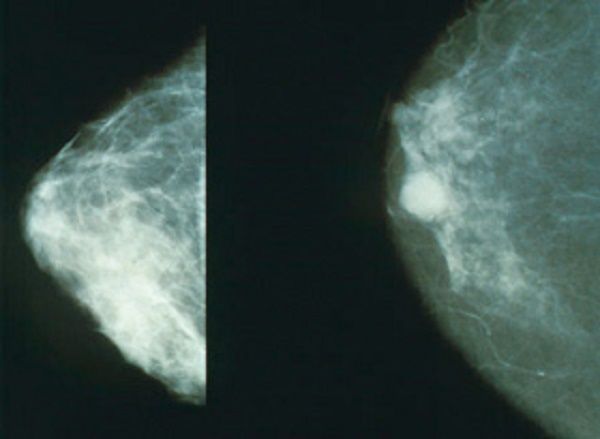

Mamografía vs. termografía

Actualmente, el método más utilizado para la detección de cáncer de mama es la mamografía, radiación que arroja una imagen anatómica del seno, mediante la cual se pueden observar formaciones atípicas en el tejido.

Aclaró que “la mamografía es un estudio anatómico, mientras que la termografía infrarroja es un análisis funcional del seno. La unión de las partes anatómica y funcional es la que daría un mejor diagnóstico”. Por ello, la forma más efectiva para detectar la enfermedad en una etapa temprana es la suma de la termografía y el ultrasonido, afirmó el científico.